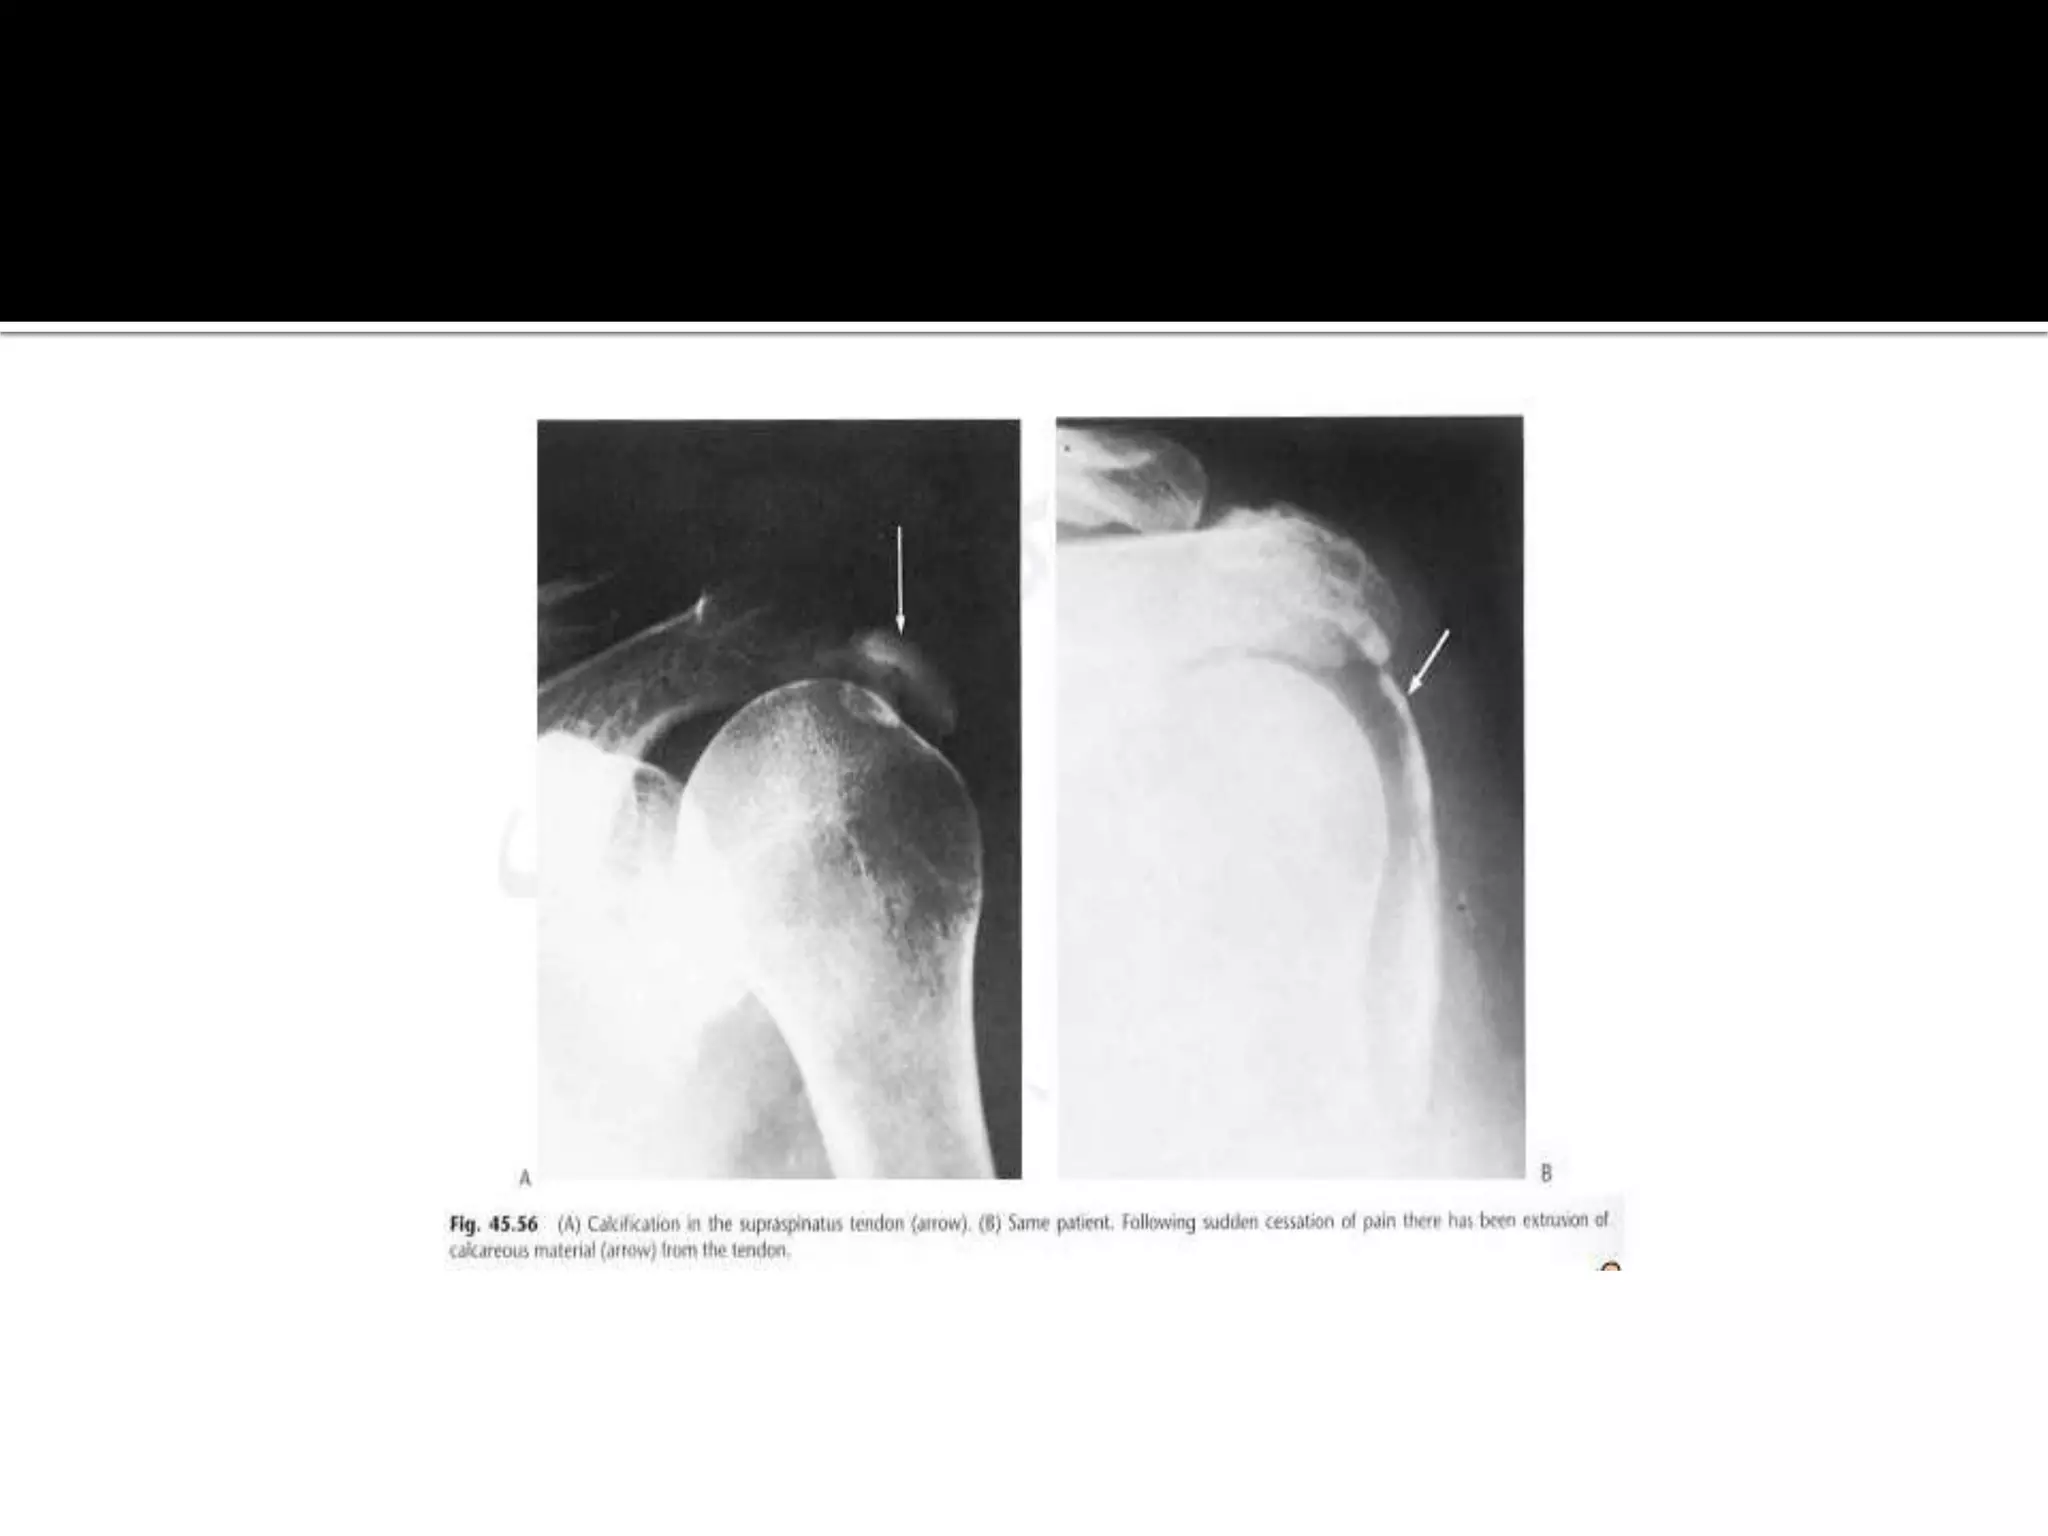

Calcification in tendons,patella,Achilles

 Due to chronic trauma or inflammation

 Rotator cuff especially supraspinatus tendon most

commonly affected

 Calcification lies directly over the humeral head in

crescentic distribution. it may be present

symptomatic patents.

Calcification in tendons,patella,Achilles Due to chronic trauma or inflammation  Rotator cuff especially supraspinatus tendon most commonly affected  Calcification lies directly over the humeral head in crescentic distribution. it may be present symptomatic patents.

• 14.

 Carpi radialisin violinists and medial collateral ligament of the knee.(pellegrini steida lesion )